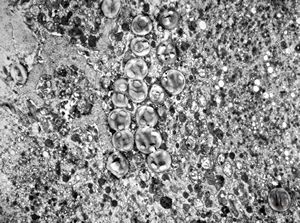

F, 24y. | molluscum contagiosum … virions

F, 24y. | molluscum contagiosum

F, 7y. | molluscum contagiosum … virions